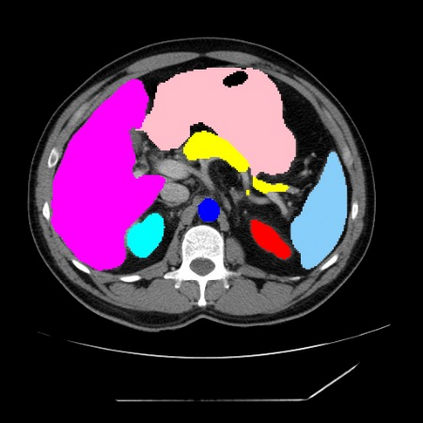

Integrating high-level semantically correlated contents and low-level anatomical features is of central importance in medical image segmentation. Towards this end, recent deep learning-based medical segmentation methods have shown great promise in better modeling such information. However, convolution operators for medical segmentation typically operate on regular grids, which inherently blur the high-frequency regions, i.e., boundary regions. In this work, we propose MORSE, a generic implicit neural rendering framework designed at an anatomical level to assist learning in medical image segmentation. Our method is motivated by the fact that implicit neural representation has been shown to be more effective in fitting complex signals and solving computer graphics problems than discrete grid-based representation. The core of our approach is to formulate medical image segmentation as a rendering problem in an end-to-end manner. Specifically, we continuously align the coarse segmentation prediction with the ambiguous coordinate-based point representations and aggregate these features to adaptively refine the boundary region. To parallelly optimize multi-scale pixel-level features, we leverage the idea from Mixture-of-Expert (MoE) to design and train our MORSE with a stochastic gating mechanism. Our experiments demonstrate that MORSE can work well with different medical segmentation backbones, consistently achieving competitive performance improvements in both 2D and 3D supervised medical segmentation methods. We also theoretically analyze the superiority of MORSE.